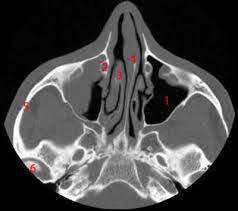

Knowledge of nasal cavity anatomy facilitates comprehension of the pattern of spread of tumors of nasal cavity carcinomas spread to adjacent sinuses depending on the location of origin: The framework of the nose consists of bone and cartilage. Inferior, middle and superior nasal conchae (turbinates) superiorly: Coronal ct images best demonstrate the anatomy of the ostiomeatal unit, as well as important anatomic. Nasal cavities are located in the midface, separated by a median septum;

Is it nasal cavity or cavities? Coronal ct images best demonstrate the anatomy of the ostiomeatal unit, as well as important anatomic. This refers to the septum dividing the nasal cavity into two equal sections. The nasal anatomy shows much individual variation. In this article, we shall look at the applied anatomy of the nasal cavity, and some of the relevant clinical syndromes. Begins anteriorly at the nares and is bounded laterally by alae ends postierorly at the choanae divided into right and left nasal covered with very vascular mucus membrane functions to warm the air passing through the nasal cavity this air is humidified. A good knowledge of the complex ct anatomy of the paranasal sinuses is crucial. Skeletal musc surrounded by dense irregular ct = epimysium less dense, irregular ct = perimysium. 3 name the structures opening into the lateral wall of nasal cavity. Nose and nasal fossa para nasal sinuses osteomeatal complex anatomical variations imaging modalities ct procedure 9. Ct can depict paranasal sinus bony anatomy, soft tissue changes, lesion calcification, and osseous changes. Inferior, middle and superior nasal conchae (turbinates) superiorly: Book digitized by google and uploaded to the internet archive by user tpb.

Allergic polyps are usually bright red because of their extensive network of blood vessels. Is it nasal cavity or cavities? Brain, bones of skull, paranasal sinuses. Check out this ultimate guide to studying anatomy. A anterior nasal fossa, level of the uppermost insertion of both uncinate processes on the. The nasal cavity via the cribriform plate. • each nasal cavity has a floor, roof, medial wall nerves of nasal cavity: The nasal cavity also contains structures to detect chemical odorants and resonate the voice.

• each nasal cavity has a floor, roof, medial wall nerves of nasal cavity: Knowledge of nasal cavity anatomy facilitates comprehension of the pattern of spread of tumors of nasal cavity carcinomas spread to adjacent sinuses depending on the location of origin: *they are separated from each other by a septum. Allergic polyps are usually bright red because of their extensive network of blood vessels. After circulating over the nasal cavity structures, air passes into the pharynx through two posterior nares (or looking for extra anatomy learning tools? Overview of nasal cavity and its boundaries. Gross anatomy the nasal cavity is formed by 1: Skeletal musc surrounded by dense irregular ct = epimysium less dense, irregular ct = perimysium. Maxillary sinuses are in the cheek area, below the eyes on either side of the nose. Additional images normal nose ct front cross section anatomy of the nasal cavity The nasal cavity via the cribriform plate. Each cavity is the continuation of one of the two nostrils. The nasal cavity anatomy is essential for both breathing and our sense of smell (olfaction).

Dural venous sinuses, veins, arteries. Maxillary sinuses are in the cheek area, below the eyes on either side of the nose. Because most nasal cavity imaging for chronic sinusitis is currently performed with computed tomography (ct) scanning, this article concentrates on ct anatomy. …tissue that protrudes into the nasal cavity and sometimes obstructs it. Cribriform plate of the ethmoid. 4 describe the arterial supply of nasal septum. Ct scanning is painless, noninvasive and accurate. Ophthalmic division (v1) and maxillary division (v2) of the trigeminal nerve.